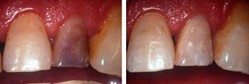

Técnicas conservadoras para la resolución y mejoramiento estético de la coloración de una o varias piezas dentarias.